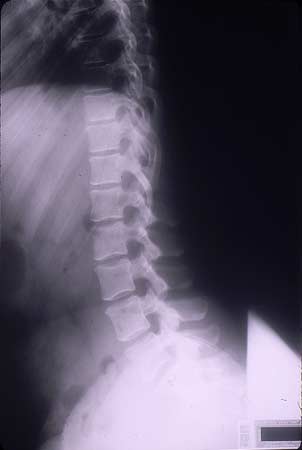

X-ray showing lumbar spine (side view)

Note: Images are shown for illustrative purposes. Do not attempt to draw conclusions or make diagnoses by comparing these images to other medical images, particularly your own. Only qualified physicians should interpret images; the radiologist is the physician expert trained in medical imaging.